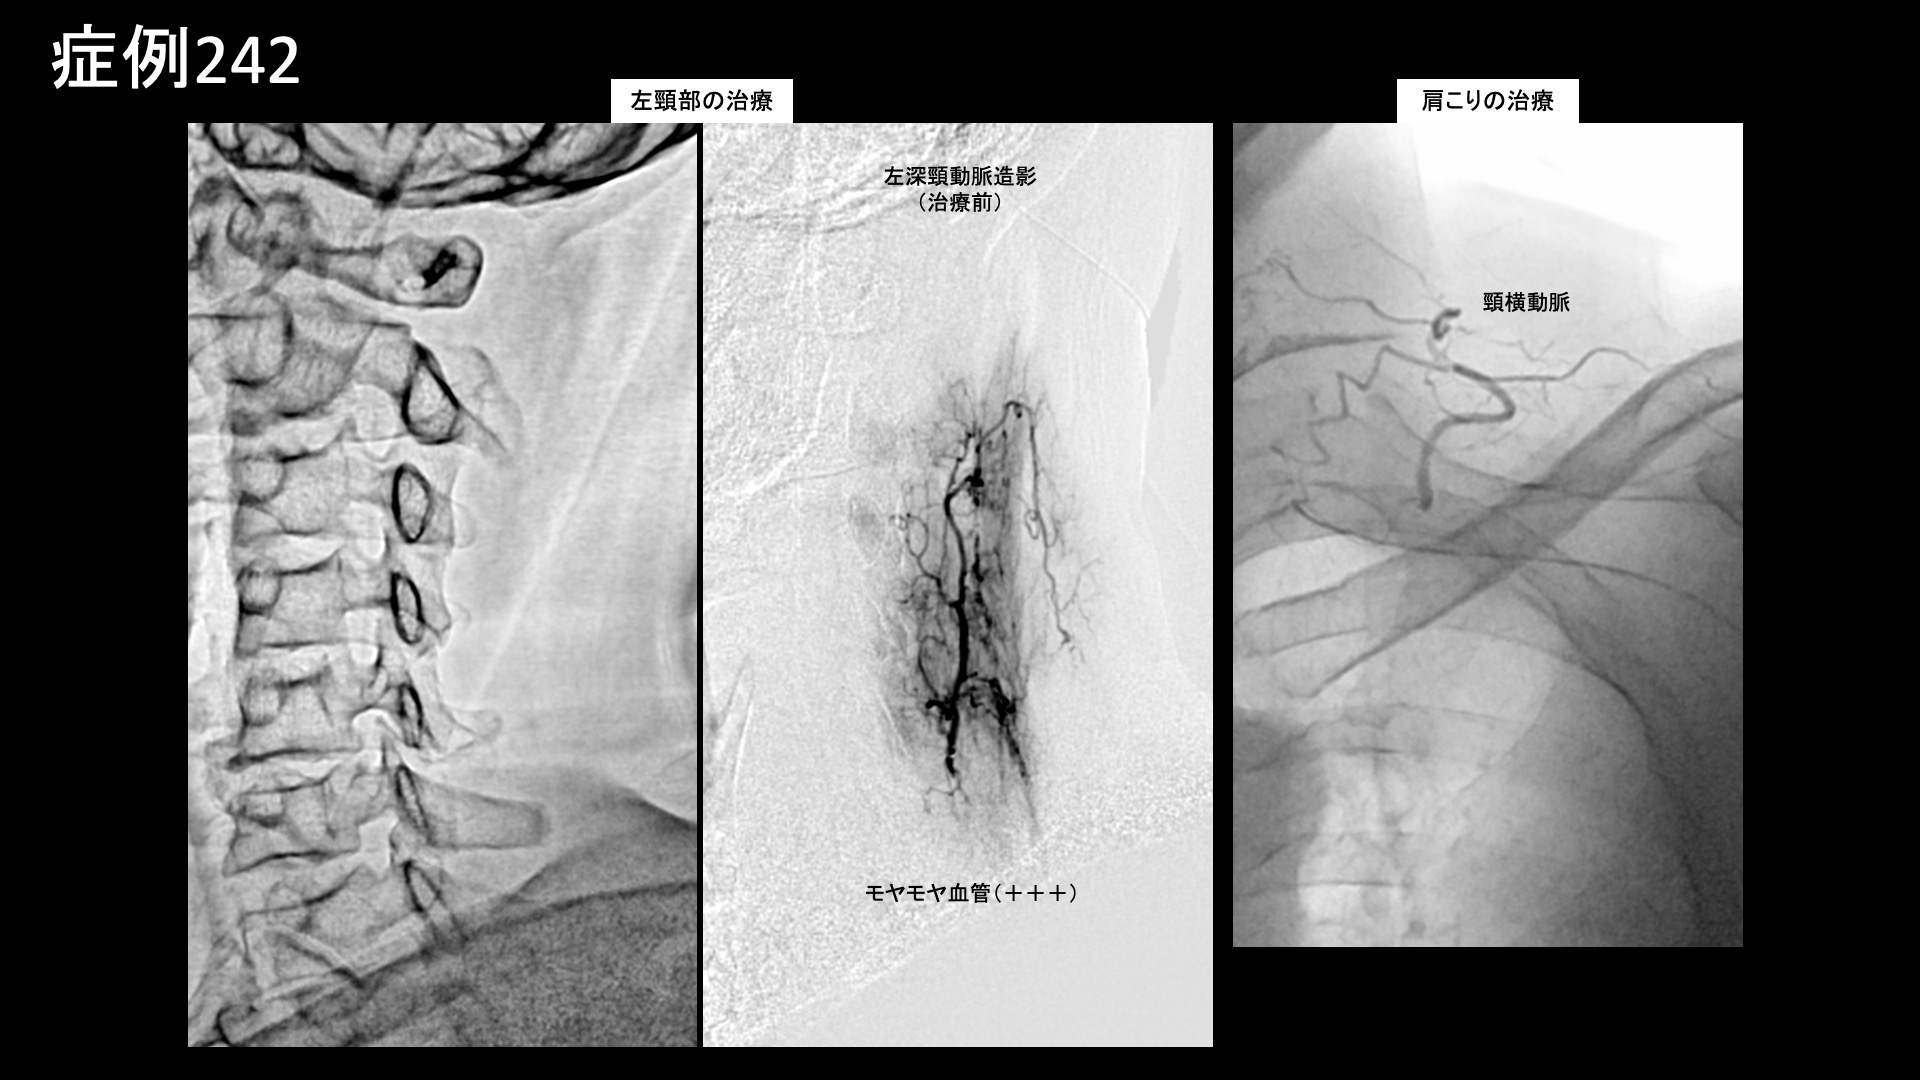

肩:肩こり・四十肩・五十肩 【50代:男性】真っすぐに座ると首から腕に激痛が・・車の運転がつらい・・重症首肩こりに対するモヤモヤ血管治療(首肩こり、頸椎症性神経根症) 2025.10.09 鴨井院長による動画解説 受診までの経過 3年前から首に違和感がありました。4ヶ月前に左肩に強烈な痛みが走り、レントゲン検査・MRI検査を受けたところ、症状の無い右肩も含めて両肩腱板に石灰沈着を認め、石灰沈着性腱板炎およびストレートネックと言われました。リハビリの方針となりましたが、効果を感じられず通院を止めていました。その後、1ヶ月前頃からは異なる症状が出てきて、背骨が真っ直ぐになるような姿勢をとると首~左肩~左腕にかけて痛むようになりました。特に椅子に座ると顕著であり、車の運転が日常的に苦痛となりました。治療方法を求めて当院を受診されました。 診察時の所見 症状の性状からは、肩関節周囲炎ではなく、頸椎症性神経根症や、重症の首肩こりである頸肩腕症候群などが疑われました。やはり、両肩関節の可動域は問題ありませんでした。一定の動作時時は見られました。首の可動域は中等度制限されており、特に後屈ではより顕著でした。レントゲンでは、頸椎は比較的保たれていました。肩関節では右側で腱板領域に粗大石灰を、左側でも少量の石灰沈着が見られました。しかしながら、エコー検査ではこれらの石灰沈着部周囲には炎症所見は見られず、陳旧性のものであることが示唆されました。一方、上腕二頭筋長頭腱周囲には水腫が見られるなど一定の炎症所見が認められました。また、棘上筋腱の部分断裂も認められました。以上より、首肩こり、および軽度の両側肩関節周囲炎(有痛性腱板損傷および、石灰沈着性腱板炎後遺症)と診断しました。治療適応と判断し、モヤモヤ血管(病的新生血管)に対する運動器カテーテル治療(微細動脈塞栓術)を受けていただきました。 治療の所見 血管造影を行うと、やはり肩関節のモヤモヤ血管よりも頸部のモヤモヤ血管の方が目立っていました。特に左頸部における深頸動脈造影においてモヤモヤ血管が濃染像として描出されました。治療後は画像上速やかに消失しました。その他複数箇所の治療を行い終了しました。 治療後の経過 治療当日から改善し、治療後2週間では、ほとんど痛みが気にならなくなりました。首を動かした際に時折つんとするような痛みが出る程度でした。よく眠れるようにもなりました。『正直半信半疑だったが、良くなってうれしい』と言われました。その後、痛みではないものの首から肩にかけてずーんと感じることはありましたが、治療後2ヶ月半になると痛み・こりともほぼ消失しました。運動習慣も取り入れていただき、様子を見ることとしました。その後も左頸部~肩の症状はぶり返すことなく順調に経過されています。尚、腱板石灰についてはやはり陳旧性のものであり、症状改善後も残存していました。新鮮なものではないため、自然吸収は期待できませんが、残存していても痛みなく過ごせる方は多いです。本症例は、頸部由来の上肢に至る神経症状をきたしている状態でした。頸椎症性脊髄症については治療効果に限界がありますが、神経根症までの段階、あるいは筋・筋膜・血行などに起因するいわゆる重症の首肩こりであれば、モヤモヤ血管に対する運動器カテーテル治療が非常に有効です。治療後は、痛みの改善だけでなく、よく眠れるようになった、眠りが深くなった、身体が軽くなったなどの感想をいただくことが多いです。首肩の不調は全身の不調につながりますので、お悩みの方はぜひご検討いただくとよいと思います。 首こりの詳細はこちら 【80代:男性】火が出るような痛みに襲われ夜も寝られず・・発症1ヶ月の頭部/顔面に生じた帯状疱疹後神経痛(帯状疱疹後神経痛) 前の記事 【50代:男性】ヘルニアによる腰部神経根症が原因の腰臀部痛に対して、減量とカテーテル治療を行い完治した症例(腰椎椎間板ヘルニア、椎間孔狭窄、神経根症、減量/マンジャロ) 次の記事